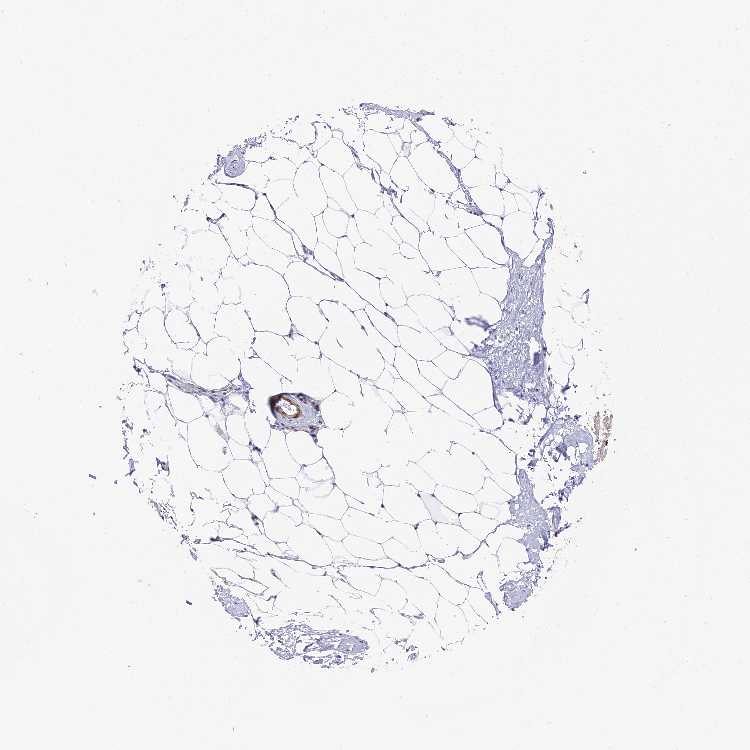

TISSUE PRIMARY DATA SOFT TISSUE Show tissue menu

SOFT TISSUE - Expression summary

SOFT TISSUE 1 - Antibody stainingi

Antibody staining in the annotated cell types in the current human tissue is reported as not detected, low, medium, or high, based on conventional immunohistochemistry profiling in selected tissues. This score is based on the combination of the staining intensity and fraction of stained cells.

Each image is clickable and will lead to virtual microscopy that enables deeper exploration of all samples and also displays staining intensity scores, fraction scores and subcellular localization as well as patient and tissue information for each sample.

Antibody HPA040759Antibody HPA040869

Chondrocytes -Medium

Fibroblasts Not detectedMedium

Peripheral nerve MediumNot detected